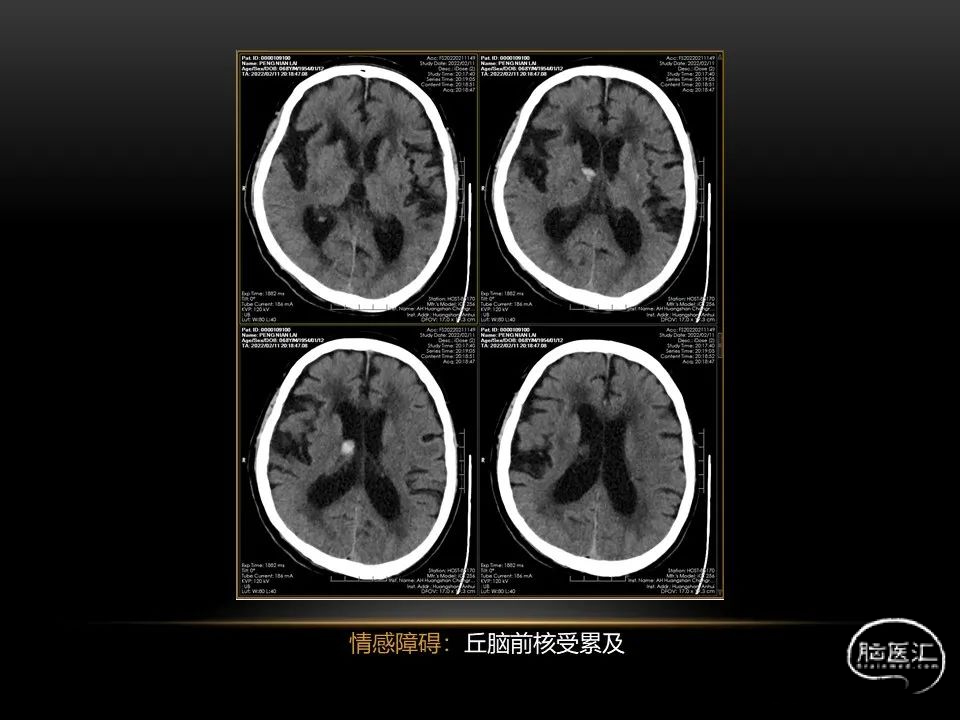

自发性脑出血临床上很常见,不同原因有特征性的出血部位。例如:基底节出血和丘脑出血大多是高血压性脑出血;脑叶出血,特别是多次复发的脑叶出血多见于老年人的脑血管淀粉样变。

自发性脑出血不仅仅累及内囊后肢才会出现偏瘫及偏身感觉障碍,病变累及大脑脚或辐射冠同样有可能有类似症状和体征。内囊、辐射冠、大脑脚等结构之间是延续的,只是不同区域不同名称而已。定位诊断需要对解剖结构概念清晰,读片准确辨认,灵活掌握。